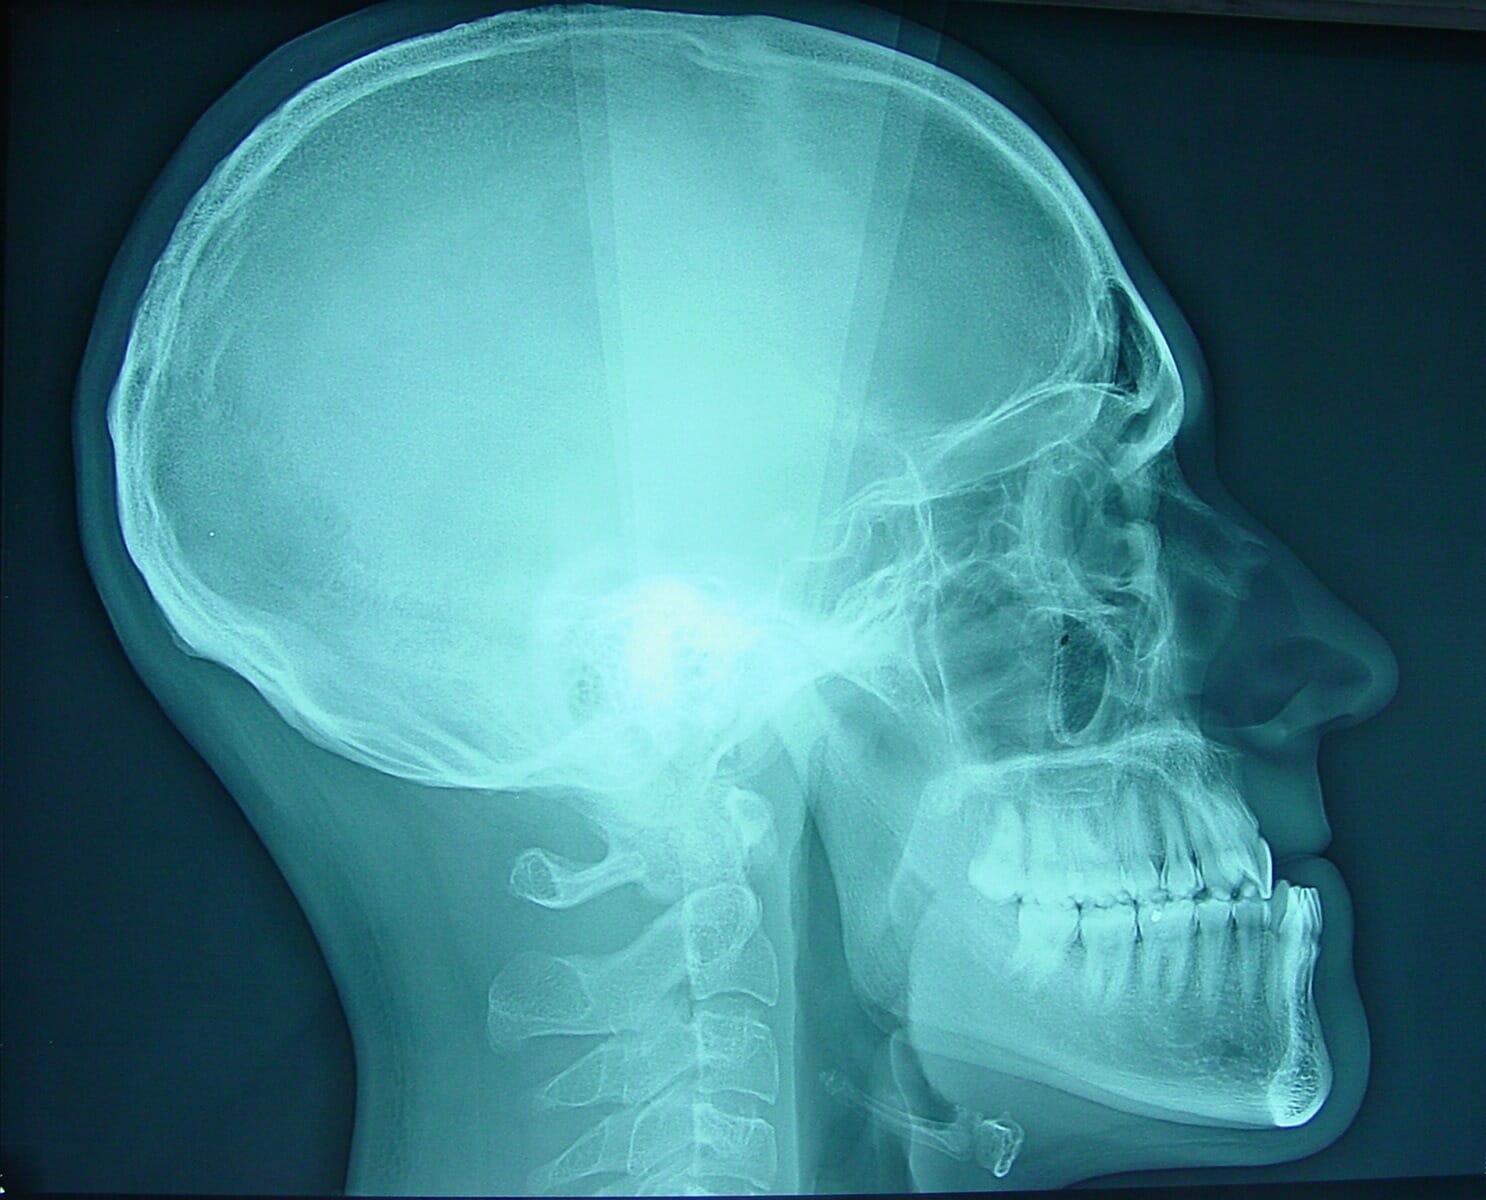

Divers examens complémentaires viennent compléter et préciser le diagnostic d’une DDM au cours de son bilan. Des clichés radiographiques standardisés (orthopantomogramme, téléradiographies de face et de profil) sont réalisés aux étapes clés du protocole orthodontico-chirurgical (début de traitement, phase pré-opératoire, phase post-opératoire). Le scanner crâniofacial ne fait pas partie du bilan pré-opératoire standard, bien qu’il soit réalisé en routine par certaines équipes. Les moulages dentaires sont utiles en début de traitement pour planifier la phase de préparation orthodontique, en cours de traitement pour apprécier l’avancée de la préparation, et en fin de préparation orthodontique afin de savoir si le patient est prêt pour le temps chirurgical. Des moulages finaux permettront de confirmer la parfaite occlusion dentaire obtenue en fin de protocole orthodontico-chirurgical. D’autre part, des clichés photographiques du visage et de l’occlusion sous différentes incidences (face, profil, trois-quart), au repos et au sourire, doivent être réalisés aux étapes clés du protocole thérapeutique. Enfin, l’analyse céphalométrique structurale et architecturale, souvent informatisée actuellement, est un outil complémentaire permettant de préciser le type de dysmorphose squelettique présentée par le patient.